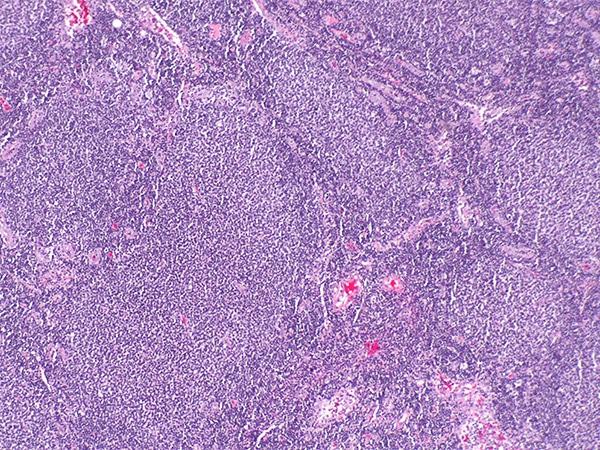

Non-Hodgkin lymphoma is the most common blood cancer diagnosed in the United States. In 2019, 74,200 people in the United States are expected to be newly diagnosed with the disease, according to data from the National Cancer Institute (NCI). About 20 percent of these cases will be classed as follicular lymphoma, which is a slow-growing type of non-Hodgkin lymphoma that arises in immune cells called B cells.

CLL and SLL are also slow-growing blood cancers that arise in B cells. According to the NCI, CLL and SLL are essentially the same disease, but have different names depending on where in the body the cancer cells accumulate. CLL cells are found mostly in the blood and bone marrow, whereas SLL cells are found mostly in the lymph nodes. The latest federal statistics show that the number of new cases of CLL and SLL was 4.5 per 100,000 U.S. men and women per year.